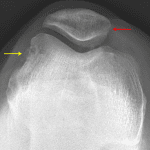

- Cortical irregularity along the medial margin of the patella and along the lateral margin of the lateral femoral condyle

- Large lipohemarthrosis

- Transient patellar dislocation with lipohemarthrosis

Cortical irregularity along the medial margin of the patella and along the lateral margin of the lateral femoral condyle concerning for impaction fractures related to transient lateral patellar dislocation. An avulsion fracture from the medial patella is also a consideration.

Large lipohemarthrosis.